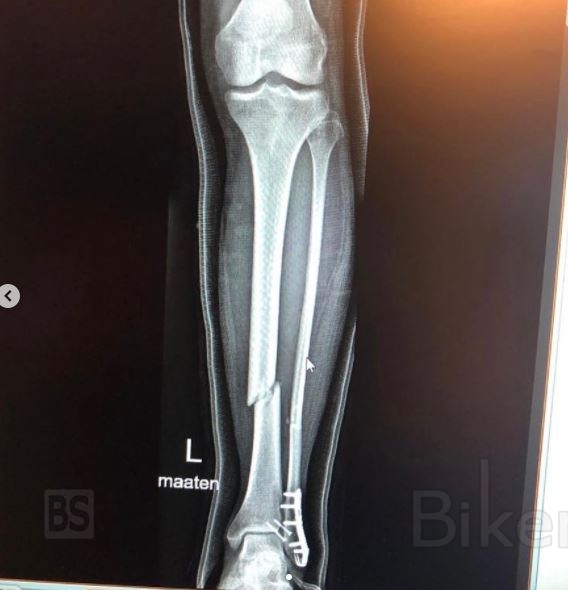

Όπως επιβεβαιώθηκε από τον ίδιο τον αναβάτη της KTM, ένα μικρό σφάλμα τον έβγαλε από την πίστα, με την ατυχία να κάνει ένα έντονο χτύπημα στο αριστερό του πόδι που προκάλεσε διπλό κάταγμα της κνήμης και της ινώδους. Παρά το γεγονός ότι Ο Kallio δεν έπεσε ποτέ από την μοτοσυκλέτα, όπως μπορείτε να δείτε στο Video.

Ο ίδιος ο 38χρονος πιλότος ενημέρωσε τους οπαδούς του στα κοινωνικά δίκτυα για τον τραυματισμό του: «Με περιμένει μια χειρουργική επέμβαση κνήμης και ινώδους, δυστυχώς μερικές φορές ένα μικρό και ηλίθιο λάθος έχει οδυνηρές συνέπειες. Δεν ήταν αυτό που είχα στο μυαλό μου για αυτόν τον αγώνα στον πάγο, θα είμαι εκτός των δοκίμων για 7 έως 8 εβδομάδες για να ανακάμψω. Ζητώ συγνώμη σε όλους που επηρεάζονται, είναι η σκοτεινή πλευρά των αγώνων, ακόμη και η άσκηση ενός χόμπι.»